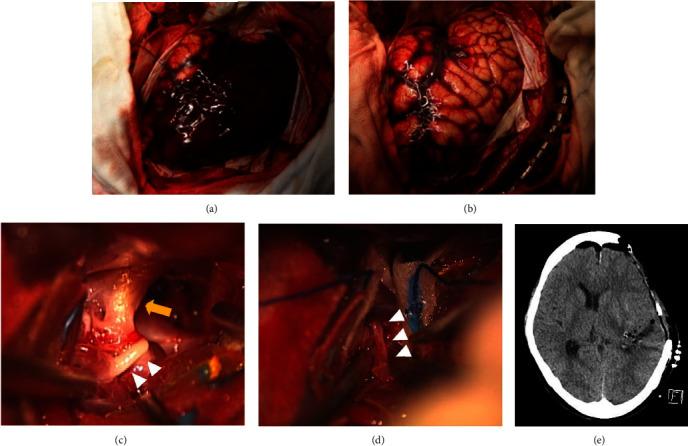

Moyamoya disease is often diagnosed after intracranial hemorrhage in adult patients. Here, we report a case of unilateral moyamoya disease treated with indirect revascularization combined with cranioplasty after treatment for acute subdural hematoma and subcortical hemorrhage. A middle-aged woman with disturbed consciousness was transferred to our hospital. Computed tomography (CT) revealed an acute subdural hematoma with left temporoparietal subcortical hemorrhage. Three-dimensional CT angiography indicated a scarcely enhanced left middle cerebral artery (MCA) that was suspected to be delayed or nonfilling due to increased intracranial pressure. Subsequently, hematoma evacuation and external decompression were performed. Postoperative digital subtraction angiography (DSA) revealed stenosis of the left MCA and moyamoya vessels, indicating unilateral moyamoya disease. Forty-five days after the initial procedure, we performed encephalo-arterio-synangiosis (EAS) using the superficial temporal artery simultaneously with cranioplasty for the skull defect. The modified Rankin Scale score of the patient one year after discharge was 1, and the repeat DSA showed good patency of the EAS. Revascularization using EAS in the second step can be an option for revascularization for hemorrhagic moyamoya disease if the patient required cranioplasty for postoperative skull defect after decompressive craniotomy.

摘要

烟雾病在成年患者中常于颅内出血后被诊断出来。在此,我们报告一例单侧烟雾病患者,在接受急性硬膜下血肿和皮质下出血治疗后,采用间接血管重建术联合颅骨成形术进行治疗。一名意识障碍的中年女性被转诊至我院。计算机断层扫描(CT)显示急性硬膜下血肿伴左侧颞顶叶皮质下出血。三维CT血管造影显示左侧大脑中动脉(MCA)强化极少,怀疑因颅内压升高导致延迟或未显影。随后,进行了血肿清除和外减压术。术后数字减影血管造影(DSA)显示左侧MCA狭窄及烟雾血管,提示单侧烟雾病。初次手术后45天,我们在颅骨缺损修补术的同时,使用颞浅动脉进行了脑动脉吻合术(EAS)。患者出院一年后的改良Rankin量表评分为1分,复查DSA显示EAS通畅良好。如果患者在减压性开颅术后因颅骨缺损需要进行颅骨成形术,第二步采用EAS进行血管重建可作为出血性烟雾病血管重建的一种选择。